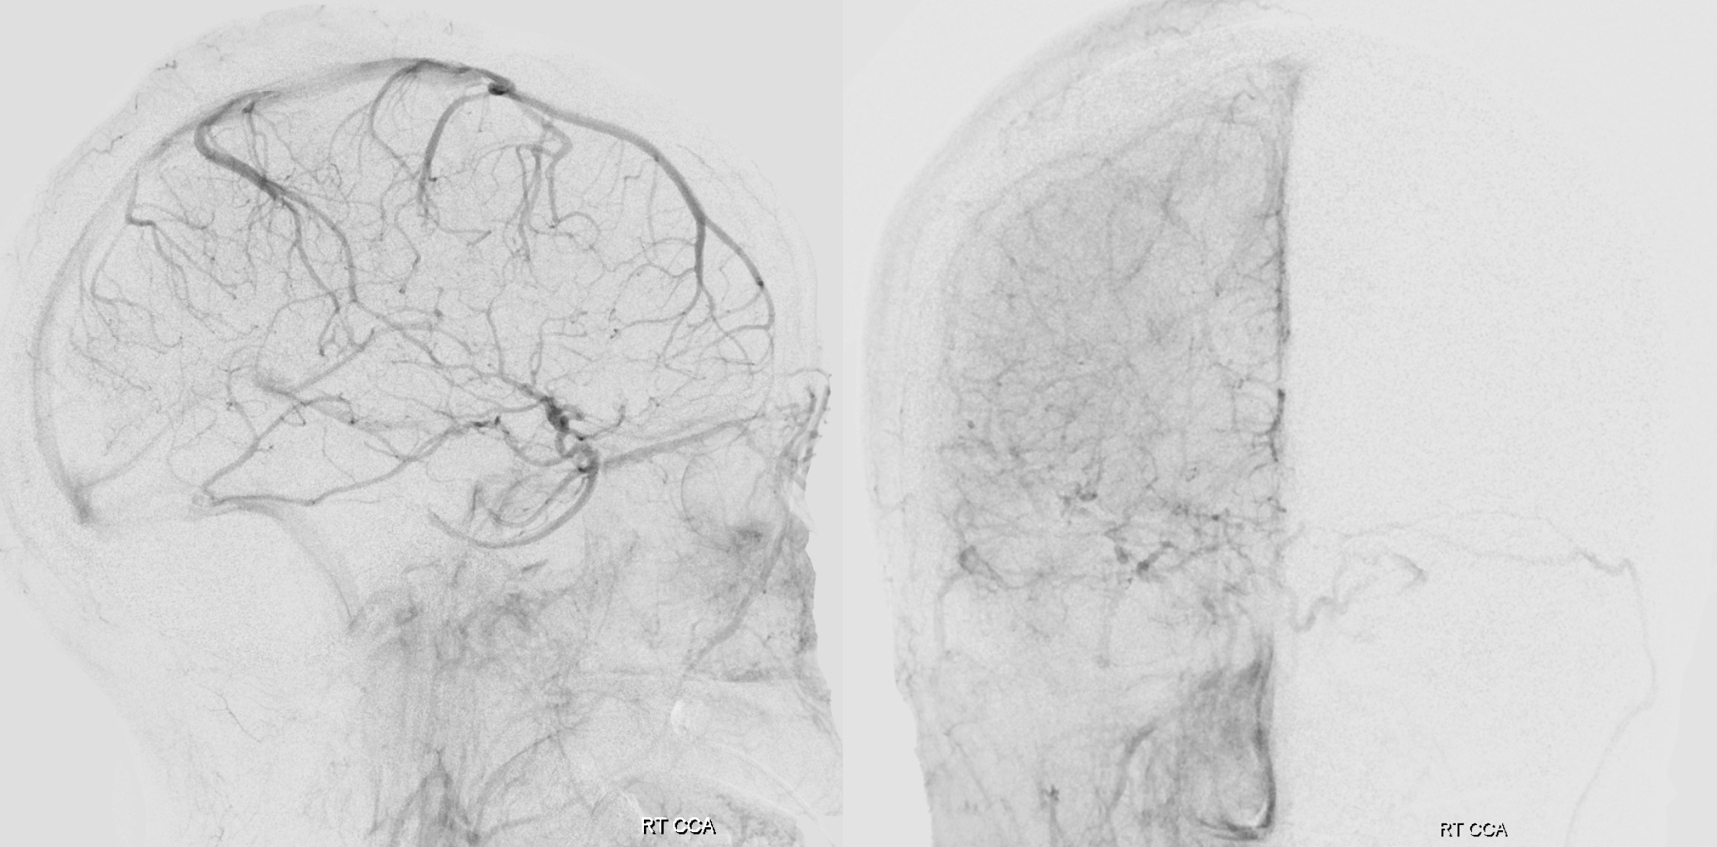

Scalp Drainage into the Cavernous Sinus

yes, all veins are connected. And no, you cant see all the veins that well by injecting arteries. Try injecting veins to see veins. The scalp also drains into the cavernous sinus — we just dont have too many scalp infections yielding cavernous thrombophlebitis to have this fact taught in med school. Here is an example of a scalp AVM draining via both superior ophthalmic veins into the cavernous sinus — case courtesy Eytan Raz MD PhD. The catheter is in the superficial temporal vein. No labels.